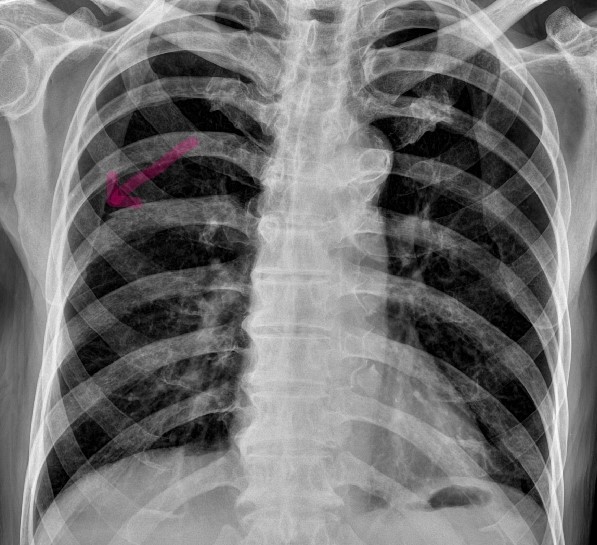

From www.semanticscholar.org

Figure 1 from A case of cough induced rib fracture with subcutaneous Rib Fracture With Coughing Rib fractures can be very painful. The central symptom is pain when you inhale. The pain is usually worse with movement, coughing, and deep breathing. A cracked rib is a type of rib fracture that can occur with a fall, car accident, sports injury, or violent coughing. When patients sustain a rib fracture, pain may preclude normal breathing or secretion. Rib Fracture With Coughing.

From www.researchgate.net

CXR (Chest X r ay) showing fractures of left 6 th , 7 th and 8 th ribs Rib Fracture With Coughing Middle ribs along the lateral aspect of the rib cage are affected most commonly. The pain is usually worse with movement, coughing, and deep breathing. Multiple fractures were more commonly seen in older patients. Breathing risks from rib fracture. Rib fractures can be very painful. A cracked rib is a type of rib fracture that can occur with a fall,. Rib Fracture With Coughing.